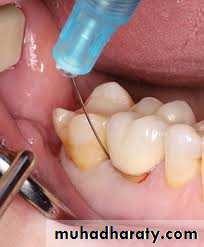

Selective Anesthesia

When symptoms are not localized or referred, the diagnosis may be challenging. Sometimes the patient may not even be able to specify whether the symptoms are emanating from the maxillary or mandibular arch. In these instances, when pulp testing is inconclusive, selective anesthesia may be helpful.

This should be accomplished by using a periodontal ligament (intraligamentary) injection. The injection is administered to the most posterior maxillary tooth in the quadrant of the arch that may be suspected, starting from the distal sulcus.

If the pain is not eliminated after an appropriate period of time, then the clinician should similarly repeat this

technique on the mandibular teeth below. It should be understood that periodontal ligament injections may anesthetize an adjacent tooth and thus are more useful for identifying the arch rather than the specific tooth